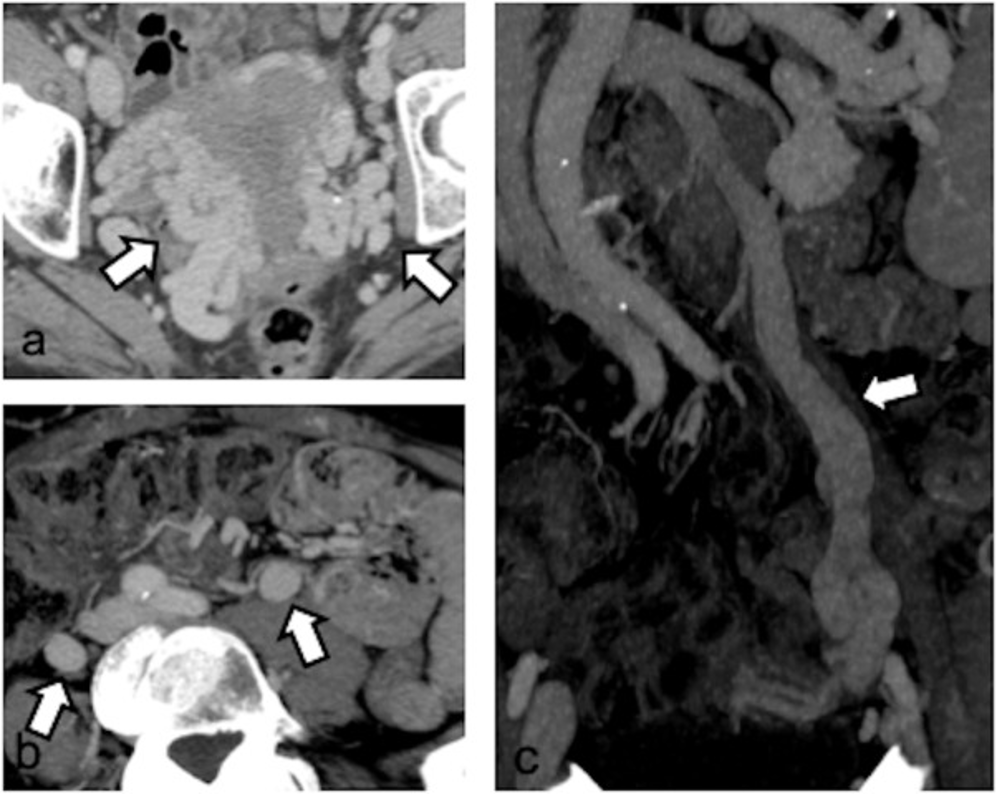

全面评估:CT检查

优势:扫描范围大,结合多平面重建(MPR)和最大密度投影(MIP),能全方位显示下腔静脉、肾静脉、卵巢静脉及盆腔静脉全貌。动脉期左侧卵巢静脉提前显影是其瓣膜功能不全的间接征象。

分级与标准:

反流分级(Hiromura):

Ⅰ级:仅左卵巢静脉反流

Ⅱ级:反流至同侧子宫旁静脉丛,未跨越中线

Ⅲ级:反流至对侧子宫旁静脉丛

直径分级(Szaflarski):

轻度:5-6 mm

中度:6-8 mm

重度:>8 mm(被认为有明确临床意义)

局限:无法做Valsalva动作,可能漏诊隐匿反流;无法直接显示血流方向;平躺体位可能低估静脉扩张程度。

图:CT显示双侧卵巢静脉III级反流:(a)双侧宫旁静脉扩张(箭头);(b)左右卵巢静脉扩张(箭头);(c) MIP重建显示左卵巢静脉扩张(箭头)